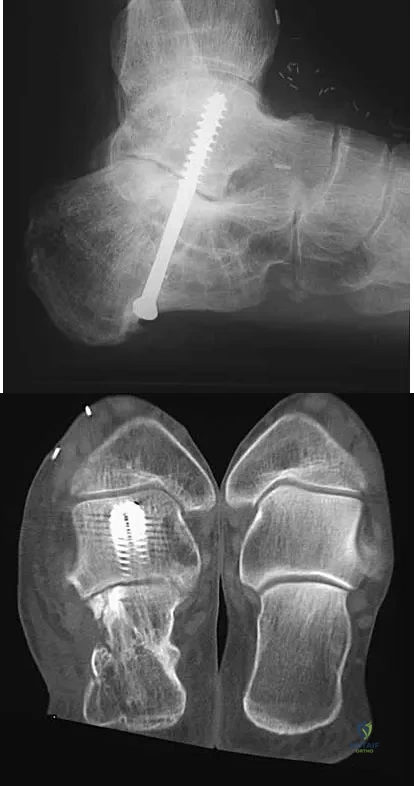

A 45-year-old man has persistent hindfoot pain that is aggravated by weight-bearing activities. History reveals that he sustained a calcaneus fracture 2 years ago, and he underwent a subtalar fusion 1 year ago. Examination reveals tenderness in the sinus tarsi and across the transverse tarsal joint. A plain radiograph and a CT scan are shown in Figures 24a and 24b. A technetium Tc 99m bone scan reveals uptake at the subtalar joint and at the transverse tarsal joints. Management should now consist of

The patient has a nonunion at the subtalar joint because of poor preparation of the arthrodesis site with incomplete removal of the articular cartilage. Clinically, he has arthritis at the transverse tarsal joint. Casting with a bone stimulator is not expected to result in a union of the subtalar arthrodesis. To address both the subtalar nonunion and the transverse tarsal joint arthritis, revision of the subtalar arthrodesis and conversion to a triple arthrodesis is the preferred option. Graves SC, Mann RA, Graves KO: Triple arthrodesis in older adults: Results after long-term follow-up. J Bone Joint Surg Am 1993;75:355-362. Haddad SL, Myerson MS, Pell RF IV, Schon LC: Clinical and radiographic outcome of revision surgery for failed triple arthrodesis. Foot Ankle Int 1997;18:489-499. Sangeorzan BJ, Smith D, Veith R, Hansen ST Jr: Triple arthrodesis using internal fixation in treatment of adult foot disorders. Clin Orthop 1993;294:299-307. Sangeorzan BJ: Salvage procedures for calcaneus fractures. Instr Course Lect 1997;46:339-346.